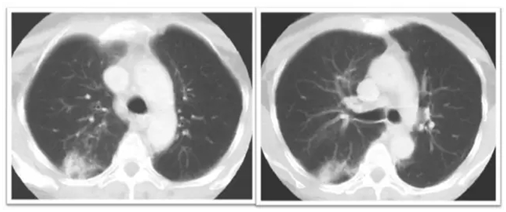

放射性肺炎的CT表現(xiàn)

早期:照射肺野內(nèi)散在的小片狀磨玻璃樣影,密度淡薄,邊緣模糊。

中期:表現(xiàn)為不按肺葉、肺段分布的肺實(shí)變,其內(nèi)可見(jiàn)有支氣管充氣征,肺泡囊、小葉間膈增厚,部分邊緣整齊,部分邊緣呈星狀,可超出放射野。

晚期:表現(xiàn)為肺野內(nèi)長(zhǎng)條狀、大片狀密度增髙影,邊緣銳利呈“刀切狀”,同側(cè)胸膜增厚,支氣管、肺門(mén)、縱膈、橫縱膈牽拉移位等肺容積縮小改變。